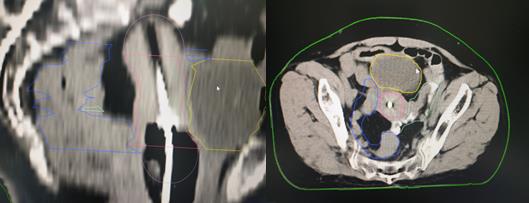

現(xiàn)代腔內(nèi)近距離放療技術(shù),即三維后裝近距離放療技術(shù),使用的放射源主要是銥192。通過先進(jìn)的計(jì)算機(jī)技術(shù),CT成像技術(shù),自動(dòng)控制技術(shù)等,實(shí)現(xiàn)三維后裝近距離放療,是一種個(gè)體化的精準(zhǔn)近距離放療技術(shù)。一般完成體外放療劑量45-50Gy后,大部分腫瘤會(huì)得到有效殺傷,但由于受到周圍腸管及膀胱等正常器官的劑量限制,宮頸腫瘤仍未達(dá)到根治劑量,還有殘留,若此時(shí)停止治療,腫瘤很快就會(huì)復(fù)發(fā)。為進(jìn)一步提高宮頸腫瘤放療劑量,此時(shí)采用三維后裝近距離腔內(nèi)照射,將小型化療的放射源送到宮腔及宮頸腫瘤部位,對殘余腫瘤單次給予很高劑量照射,而周圍正常組織照射劑量極速下跌,完美的實(shí)現(xiàn)高劑量殺滅腫瘤,正常組織受到較低劑量的影響,從而提高腫瘤患者的生存年限及生存質(zhì)量。